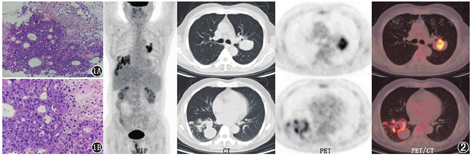

患者男,59岁,因"无明显诱因出现咳嗽、咳痰,间断痰中带血5个月余,自觉症状加重半个月"就诊。体格检查:双肺呼吸音粗,未闻及干湿性啰音。胸部CT平扫示双肺多发最大径在5.0 cm以内的软组织结节及肿块。血清甲胎蛋白(alphafetoprotein, AFP)>1 000.0(正常参考值范围:0~7.0) μg/L。既往乙型肝炎病毒携带史20年。临床疑诊肝癌肺转移,行CT引导下左肺占位穿刺活组织检查,病理结果为腺癌(图1),结合免疫组织化学检查结果考虑为肝细胞肝癌肺转移。后患者行18F-FDG PET/CT显像,结果示双肺病灶18F-FDG摄取明显增高,其余部位未见异常代谢增高区(图2)。外院肝脏增强CT检查未见异常。经多学科会诊后,临床诊断为肺肝样腺癌(hepatoid adenocarcinoma, HAC),随访患者生存期为6个月。HAC是1种罕见的原发于肝外、同时具备肝样分化征象和腺癌成分的特殊类型癌,其在病理学和免疫组织化学上有着类似于肝细胞肝癌的组分。患者无肝脏病变时,明确诊断需结合影像学与病理结果,血清AFP升高具有重要的诊断提示意义。如患者AFP明显升高,而肝脏常规检查未见异常病灶,应行18F-FDG PET/CT检查,以明确原发灶部位并进行分期。